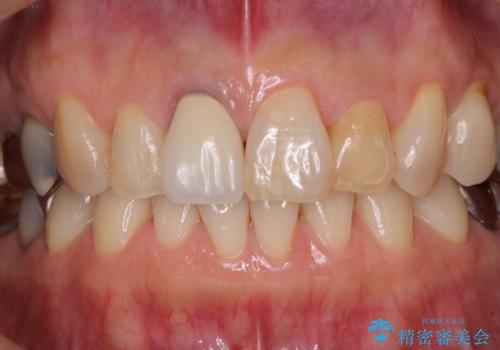

- 近医にて奥歯の抜歯が必要と言われたとのことで来院された患者様です。

診断の結果、奥歯は歯根が破折しており、抜歯が必要な状況でした。

インプラントあるいはブリッジによる補綴治療が考えられましたが、前後の歯が大きな銀歯であったため、オールセラミックブリッジにより3本の歯を審美的に仕上げることとしました。

前歯は神経を取り除いて変色した歯や金属の縁が見える歯などがあり審美的に気になっていましたが、治療するかどうかは悩んでいらっしゃいました。